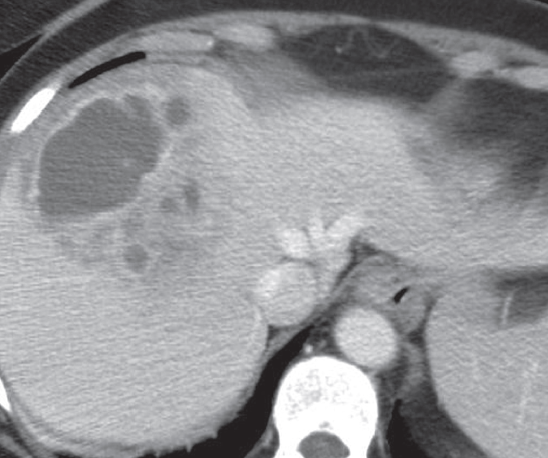

- CT(computed tomography)

- 초음파에 비해 민감하고, 농양의 위치나 크기 확인에 용이하다.

- 조영제 사용으로 인한 알러지 반응, 신장기능의 악화 가능성이 있다.